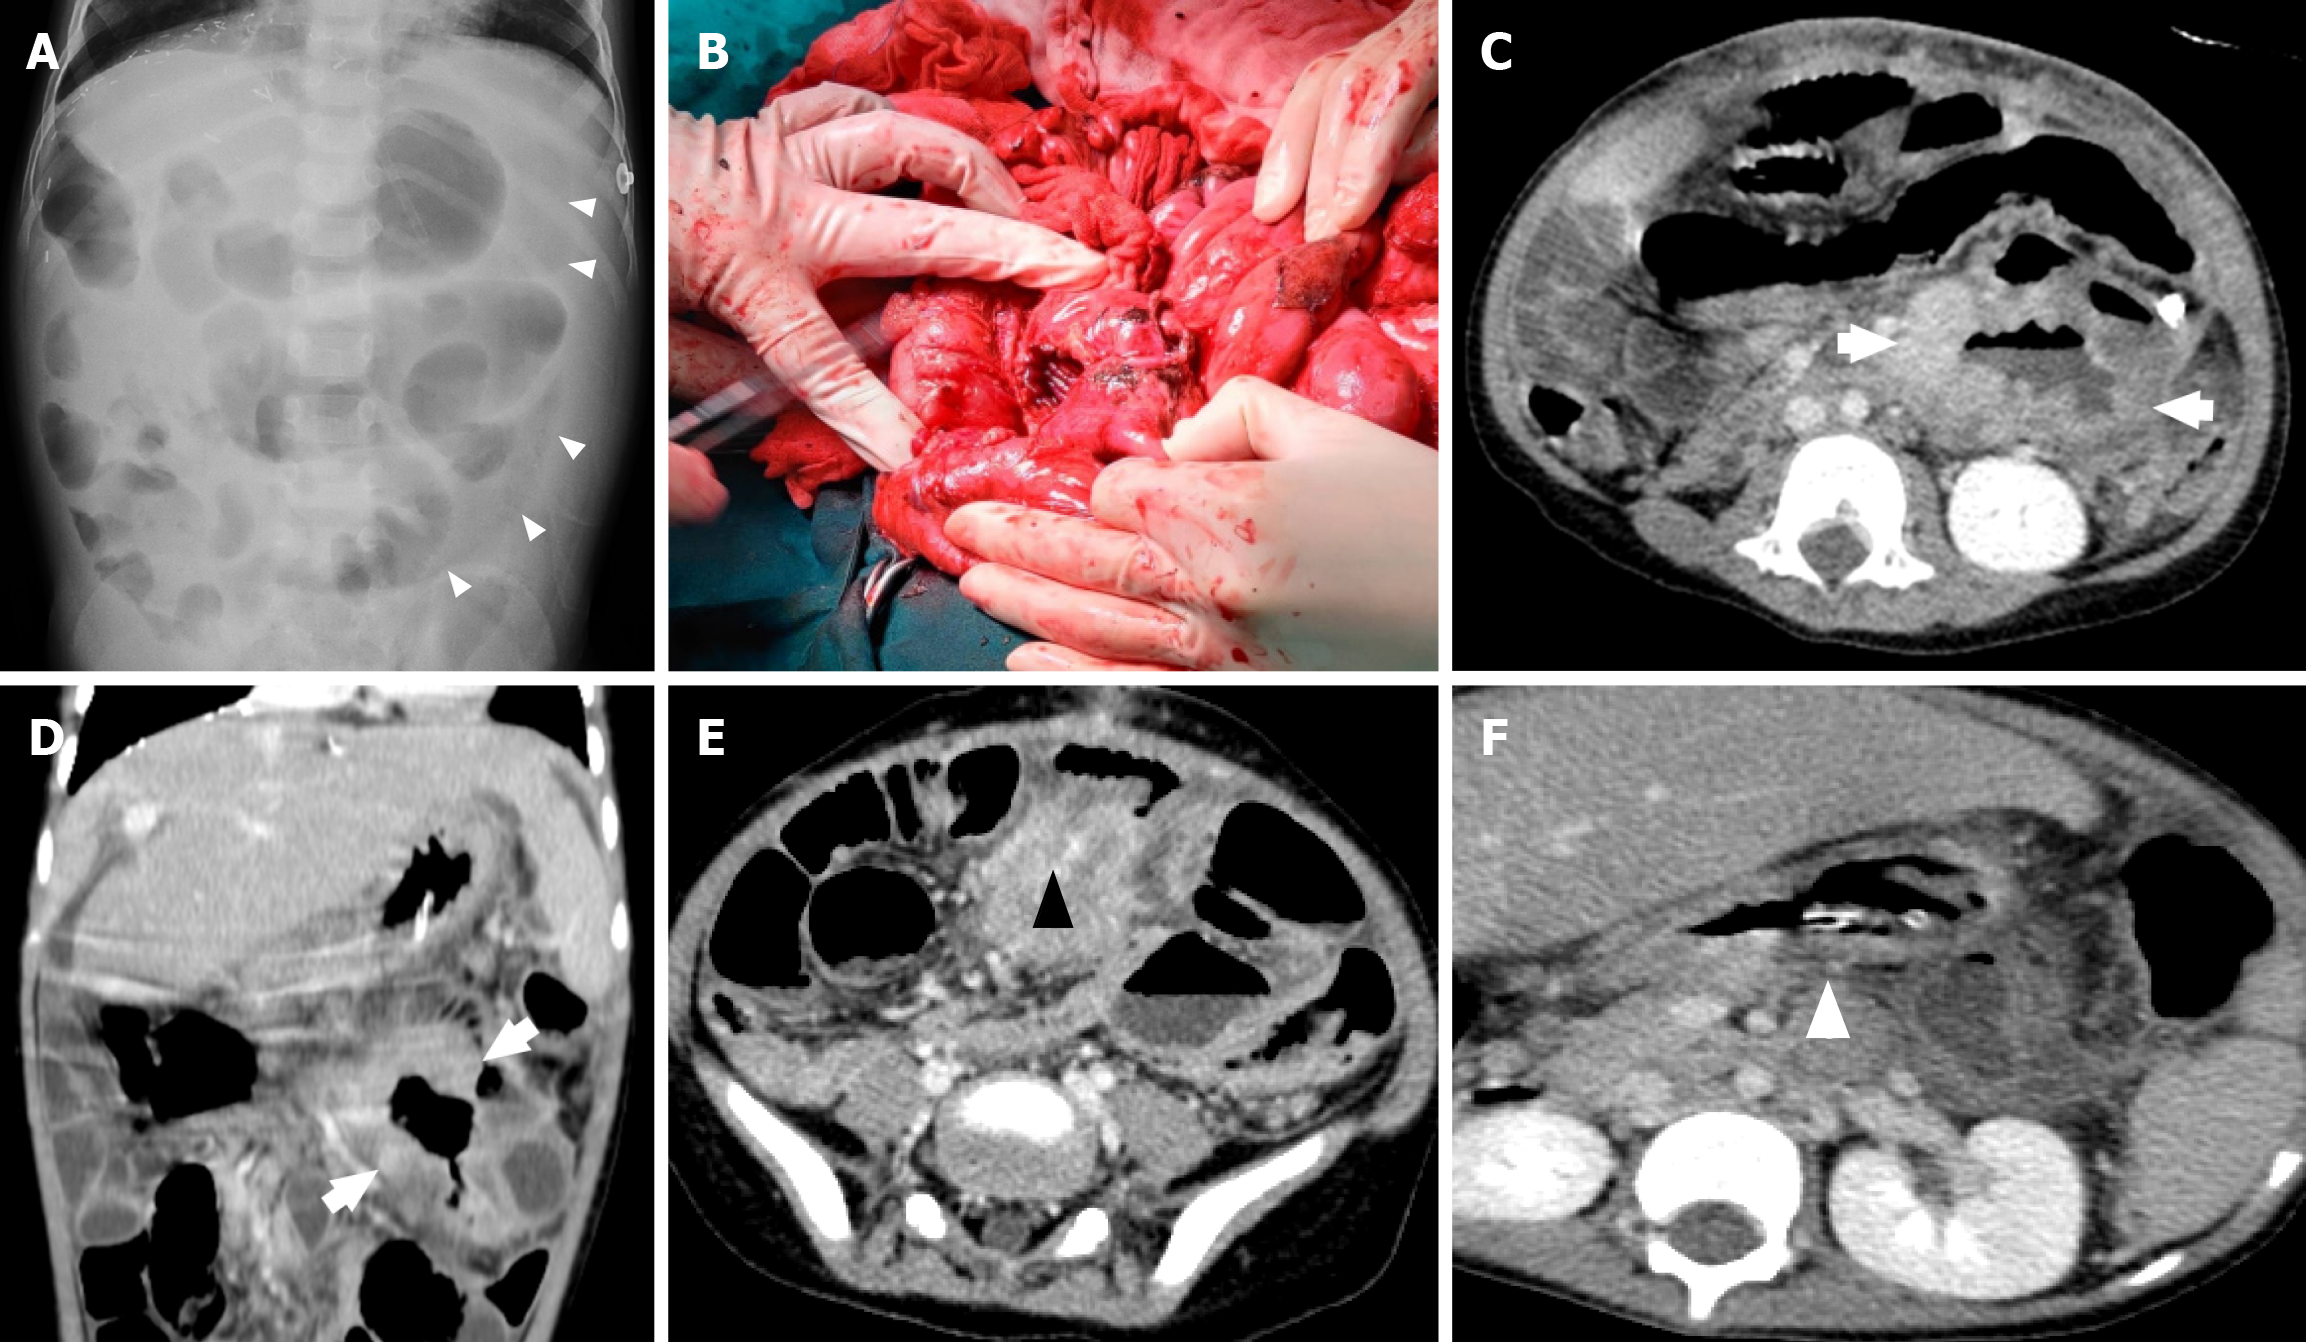

Figure 2 A 4-year-old boy who underwent liver transplantation 3 years ago presented with a subacute fever and abdominal pain.

Supine abdominal radiograph showed free intraperitoneal air (white triangle in Figure 2A) and an infiltrative lesion at the duodenojejunal site, a 6 cm mass with a large perforation site at the duodenojejunal junction. Computed tomography images 7 days after exploratory laparotomy showed segmental, irregular bowel wall thickening and aneurysmal dilation of a jejunal loop in the left upper to mid-abdomen (white arrows), matted mesenteric lymph nodes (black triangle), and an enlarged para-aortic lymph node (white triangle). A: Abdominal X-ray; B: Operative finding; C-F: Computed tomography abdomen (cross section).